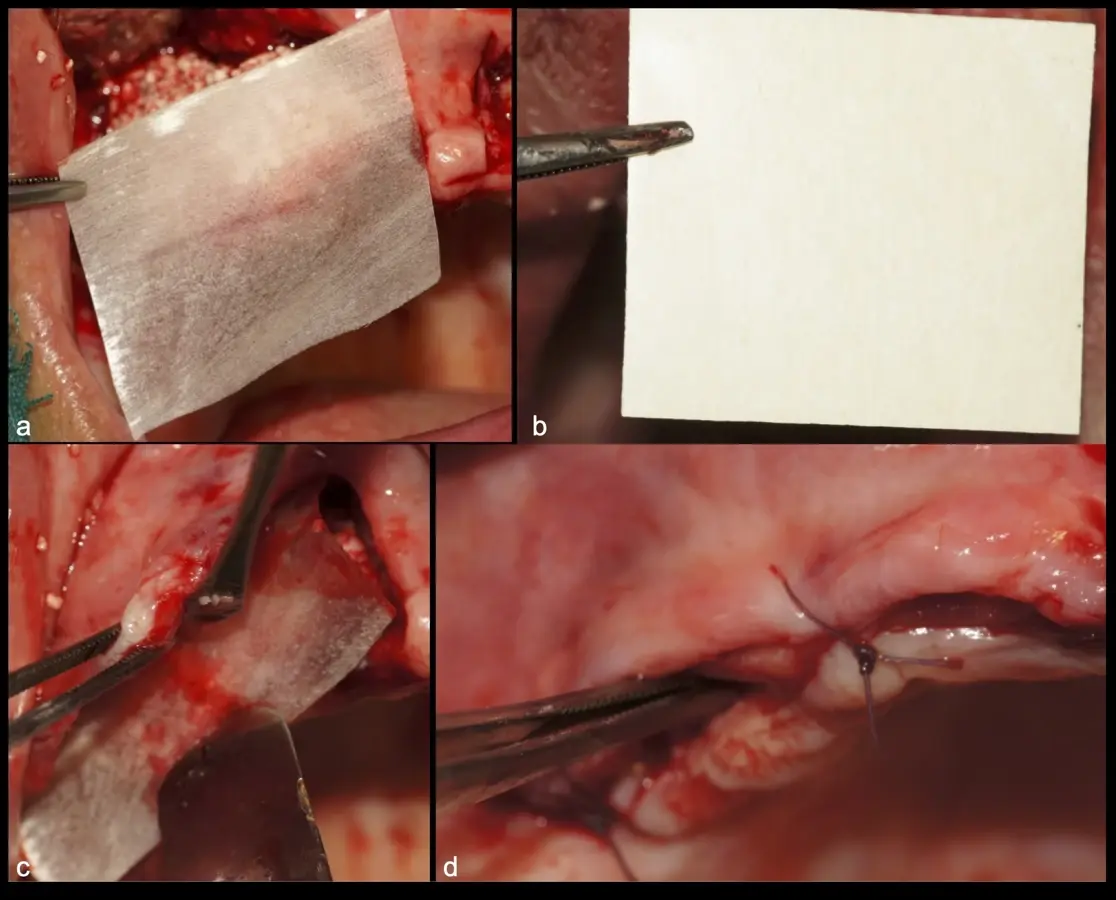

Figura 33. Pasos de la colocación de membranas de barrera y cierre sin tensiones (a - d).

Figura 40. Secuencia de fijación y modelado del bloque óseo con inserto de corte, eliminación de ángulos agudos (a-d).

Figura 41. Modelado del bloque óseo con inserto plano de punta diamantada (a) para redondear los ángulos agudos y así evitar una dehiscencia o fenestración de los tejidos blandos (b).

Figura 44. Pasos para la colocación de la membrana de barrera (a - d).

**No momento, os artigos estão disponíveis apenas na versão original em espanhol.